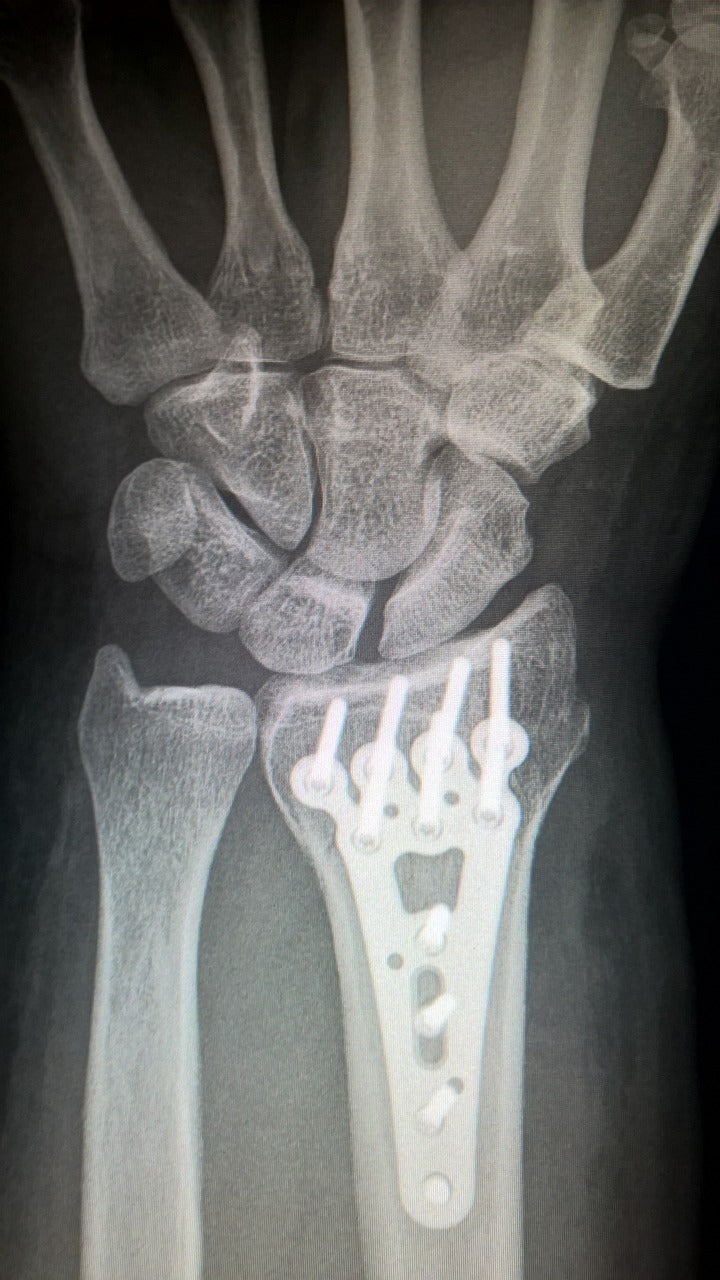

Radiografía de muñeca abierta y débil